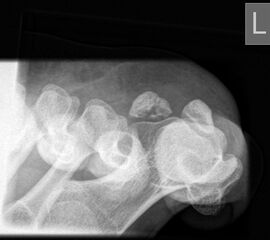

pa (posterior-anteriore) axiale Aufnahme der Sesambeine (Sprinteraufnahme)

Positionierung:

• Patient in Bauchlage, Knie durch Schaumstoffmatte unterstützt.

• Zehen in maximaler Dorsalextension.

• Zentralstrahl fokussiert auf das Großzehengrundgelenk.

• Röntgenröhre 0° vertikal.

• Filmposition horizontal.

Kennzeichen des Röntgenbildes:

• Tangentiale Abbildung des Sesambeingleitlagers.

• Abbildung des Vorfußreliefs.

• Pathologien der Gleitrinne sind gut erkennbar.

• Dislokation der Sesambeine aus der Gleitrinne sind gut erkennbar.

• Abbildung von Protrusionen einzelner Metatarsalia oder Sesambeine.

Besondere Anmerkungen zum Beispielbild:

• Sehr kräftig ausgebildetes mediales Sesambein bei einem Patienten mit chronischen Druckbeschwerden an dieser Stelle.

• Beide Sesambeine sind in der Gleitrinne zentriert.

Zur Vollansicht und zum Lesen der Bildbeschreibung bitte die Bilder anklicken.